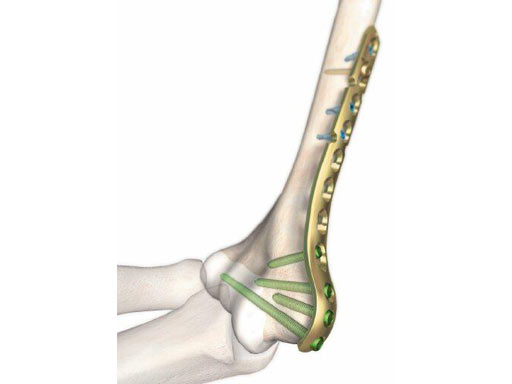

The LCP Distal Humerus has been developed for fractures in the metaphyseal area that may reach into the shaft. The distal end is anatomically contoured to the distal humerus, with three isolated round combination holes. This new round hole allows to use 3.5 conventional cortical screws to facilitate optimal screw positioning in the joint block of the distal humerus. The screws in the distal section are angled to allow optimal fixation of the screws without penetrating the joint. The reconstruction cuts in the plate shaft, allowing easy and accurate bending of the plate to adapt to the variance of the diaphyseal anatomy. The LCP Distal Humerus is available in titanium and stainless steel, in five different lengths with 7, 9, 11, 13 and 15 holes.